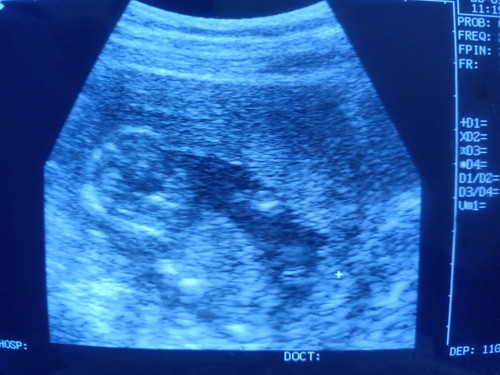

อยากทราบว่า คุณแม่ท่านอื่นๆ ที่อายุครรภ์ 30w น้องกลับหัวรึยังครับ ลูกสาวผม คุณหมอ ซาวด์ดู บอกว่าน้องกลับหัวแล้ว ตื่นเต้นมากๆเลย ท้องแรกด้วย ลูกก็ดิ้นบ่อย แม่ก็กินเยอะมาก